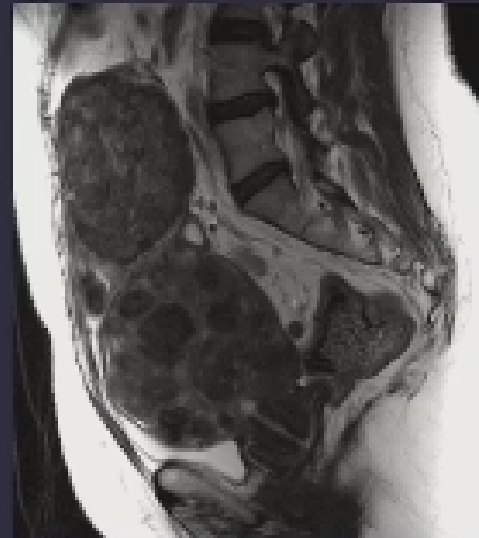

本研究的目的是比较子宫肌瘤栓塞治疗和手术治疗的中期结果。121名有生育计划的子宫内膜肌瘤大于4cm的患者被随机选择接受子宫动脉栓塞(UAE)或子宫肌瘤切除术。

我们比较了这两种方法的有效性和安全性以及它们对患者生育能力的影响。58例栓塞和63例子宫肌瘤切除(42例腹腔镜下,21例开腹)。118名患者完成了至少12个月的随访;整个研究人群的平均随访时间为24.9个月。